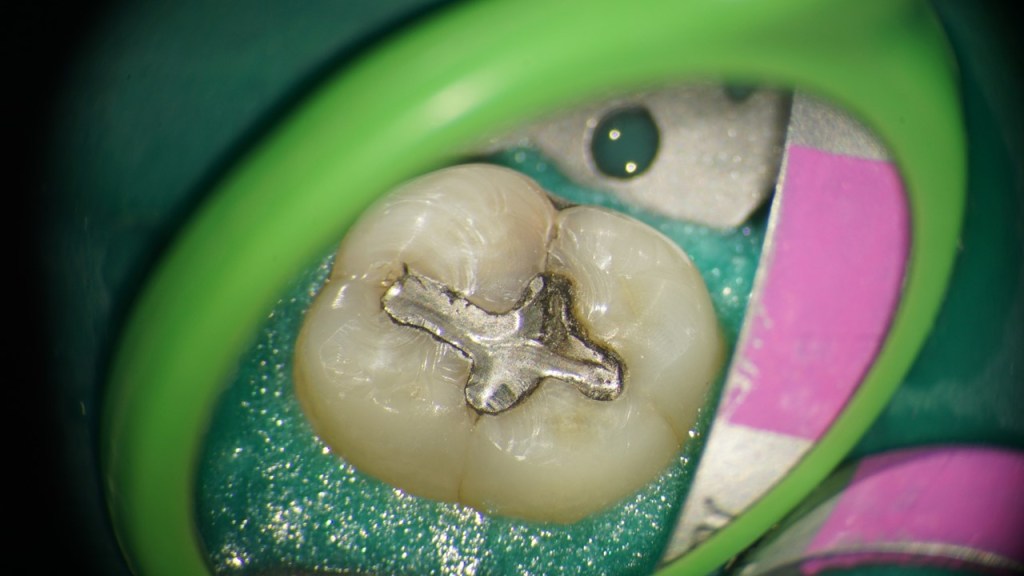

This is a “garden variety” endo. The best time to refer a case to an endodontist with a microscope is before the pulp has been touched. That way, the endodontist can control how much of tooth structure is removed to complete the endo. In this case, I had to chase all the cracks before restoring